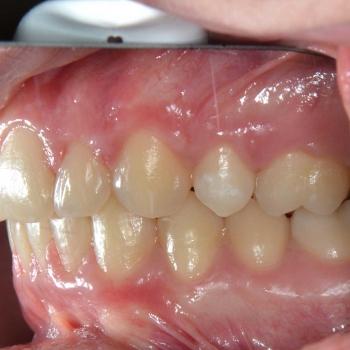

A kezelést hagyományos fém fogszabályozóval kezdtük el, melyet bite turbo harapásemelővel egészítettünk ki. A kezelés későbbi fázisában a szimmetria megteremtése érdekében eltávolításra kerül a bal felső maradó 4-es fog is és ezzel párhuzamosan különböző intermaxilláris gumihúzásokat vezettünk be.

Benjamin sportolókhoz méltő fegyelmének köszönhetően a kezelés végére egy esztétikailag és funkcionálisan is kimagasló eredményt érhettünk el.

A kezelés teljes időtartama: 2 év 3 hónap